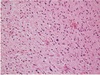

Hypercellular, angiogenesis, necrosis. Glioblastoma

Microvascular proliferation is noticeable in this GBM

GBM with pseudopallisading necrosis

Array of nuclei surrounding necrosis GBM